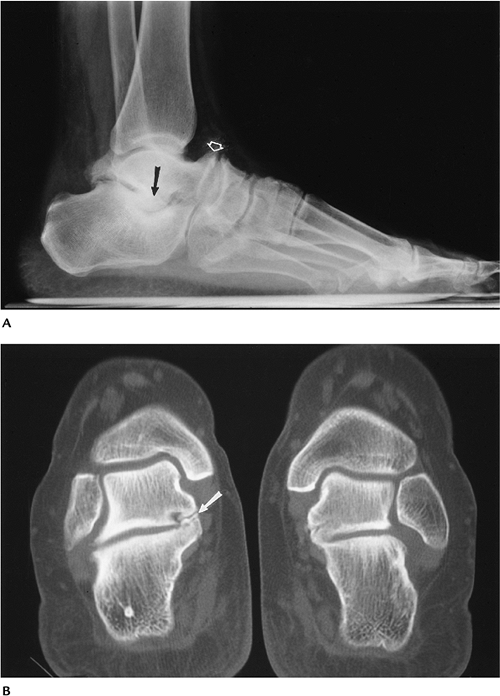

Soft Tissue Trauma/Overuse Syndromes: Sinus Tarsi Syndrome

Patients with sinus tarsi syndrome

present with lateral ankle or hindfoot pain and tenderness over the

sinus tarsi to palpation. Most patients present with a history of ankle

sprain or inversion injury (70%). -

Cause may be related to calcaneofibular ligament tears, capsular hypertrophy, and space-occupying lesions.

-

Imaging of the tarsal canal and sinus can be accomplished with ultrasound, CT, or MRI. MRI is preferred in our experience.

Surgical repair of ligament tears or decompression of masslike lesions typically is performed.

![]() |

FIGURE 6-61 Sinus tarsi syndrome. Sagittal T1-weighted (A) and T2-weighted (B) images showing abnormal signal intensity in the tarsal sinus and bone erosions (arrows).